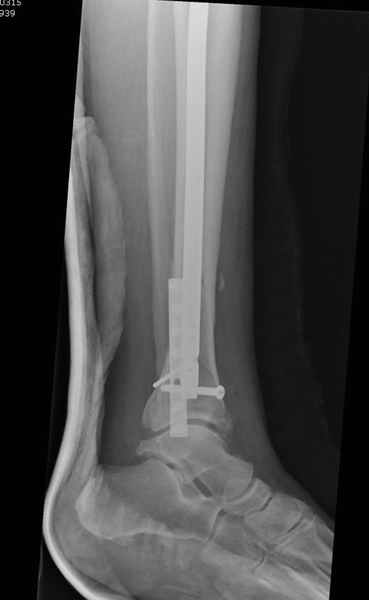

спрашивает что делать с больным который поступил недавно, фермер 55 лет падение при пьяной драке в баре, года два назад перенес операцию на лодыжке, на снимках и КТ перелом без вовлечения сустава,

Повреждение такой локализации, на которой применимы и аппарат (классический Илизарова или гибридный), пластина, особенно Locked Plate, и гвоздь с блокированием. В нашей клинике был бы выполнен закрытый интрамедуллярный остеосинтез. Желательно использовать гвоздь с возможностью провести более чем 2 обычных фронтальных винта в дистальном отломке.

Здесь мы использовали новый Synthes Nail с дополнительными дырками, в проксимальной части 4: по две косых и поперечные (один стандартный а другой динамический), в дистальной части две поперечные, прямая и косая. Вес больного более 120 кг, нагрузку начнем через месяц.

Получилось красиво, поздравляю. Вверху можно было ограничиться одним винтом во фронтальное статическое отверстие, зачем два 45-градусных?

При такий спирали задний край tibia может быть сломан - нет ли этого в данном случае? На всякий случай можно было ввести 1-2 винта 4,5 мм спереди назад мимо гвоздя. Хотя самый дистальный блокирующий винт, возможно, зацепил этот отломок. А какой тут диаметр гвоздя и locking винтов?